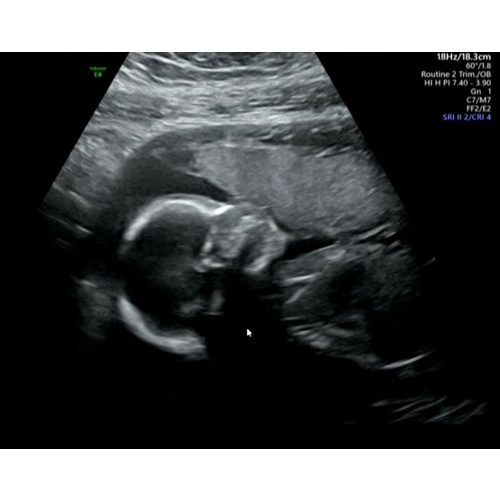

Volgens mij is het bij jou het stuk rechts boven. Je herkent het omdat het een beetje een onregelmatig, wat lichter stuk is.

Bij 12 weken neemt je placenta het pas over. Daarnaast gaat het vlies dat je ziet ook nog verschuiven. Nu krijgt de baby nog zijn of haar voeding van de dooierzak (zie ik hier ook niet op de foto, maar dat zal aan de diepte van de foto liggen).

Je ziet het pas goed met de 20 weken echt. Hier ligt zijn gezicht tegen de placenta. Bij mij lag de placenta voor en laag.

Nu nog wat te vroeg dus? Was hier 7+5 met de echo. Maar ik gok ook dat hij nu aan de rechterkant op de foto zit.

Rechterkant bovenaan de foto, bij mij zag het er namelijk exact hetzelfde uit en toen zei de verloskundige dat, dat de placenta was, en inderdaad de hele zwangerschap zat hij daar 😋

Was jouw echo ook inwendig gemaakt? Ik denk dat het volgens de ramzi theorie een jongetje wordt ☺